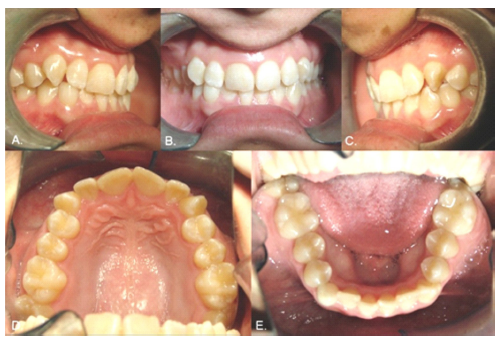

Case 1

Male, 12 years old. Clinical examination revealed that the inferior left canine was the only primary tooth still present (Fig. 1). The panoramic radiograph showed that the 3.3 was in a type 1 transmigration (Fig. 2A). The cone beam computed tomography (CBCT) showed that the crown of the transmigrated canine was very close to the adjacent incisors’ roots (Figs. 2 B and C). Despite the recommendation for surgical removal or even orthodontic traction, the parents chose not to treat the transmigrated tooth and instead to follow up with periodic radiographs.